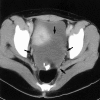

Autoimmune hemolytic anemia associated with an ovarian teratoma is a very rare disease. However, treating teratoma is the only method to cure the hemolytic anemia, so it is necessary to include ovarian teratoma in the differential diagnosis of autoimmune hemolytic anemia. We report herein on a case of a young adult patient who had severe autoimmune hemolytic anemia that was induced by an ovarian teratoma. A 25-yr-old woman complained of general weakness and dizziness for 1 week. The hemoglobin level was 4.2 g/dL, and the direct and indirect antiglobulin tests were all positive. The abdominal computed tomography scan revealed a huge left ovarian mass, and this indicated a teratoma. She was refractory to corticosteroid therapy; however, after surgical resection of the ovarian mass, the hemoglobin level and the reticulocyte count were gradually normalized. The mass was well encapsulated and contained hair and teeth. She was diagnosed as having autoimmune hemolytic anemia associated with an ovarian teratoma. To the best of our knowledge, this is the first such a case to be reported in Korea.